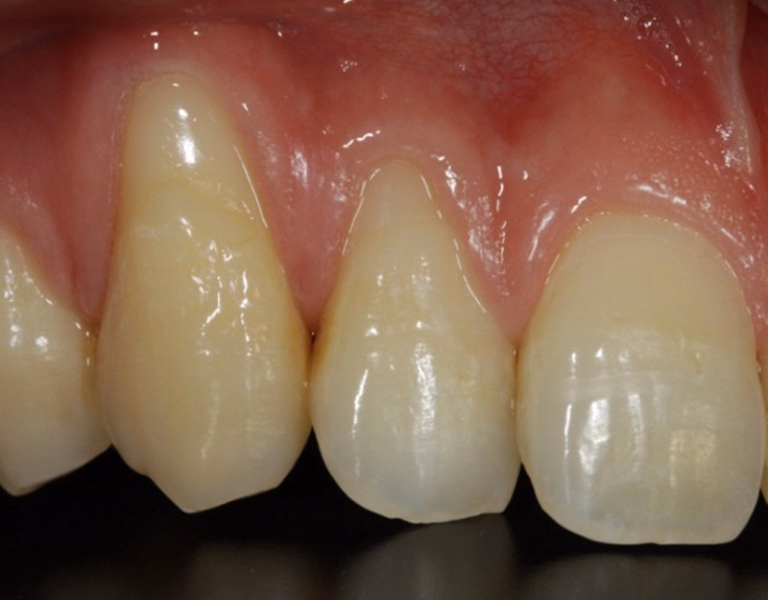

治療前後写真

治療前

治療後

40代・女性

前歯の治療を他院で行っていたが、これ以上治せないとのことで当クリニックでの治療を希望

治療内容

- ① CT検査・サージガイド作製

- ② 抜歯と同時にインプラント埋入(抜歯即時埋入)

- ③ 結合組織移植

- ④ セラミッククラウン+ラミネートベニア装着

約8ヶ月

902,000円(税込・自費診療、保険適応外)

- 術後の腫脹・疼痛・出血

- インプラントが骨結合しない可能性

医院コメント

噛む機能だけでなく口元のバランスも改善。

定期メンテナンスにより長期安定を目指します。